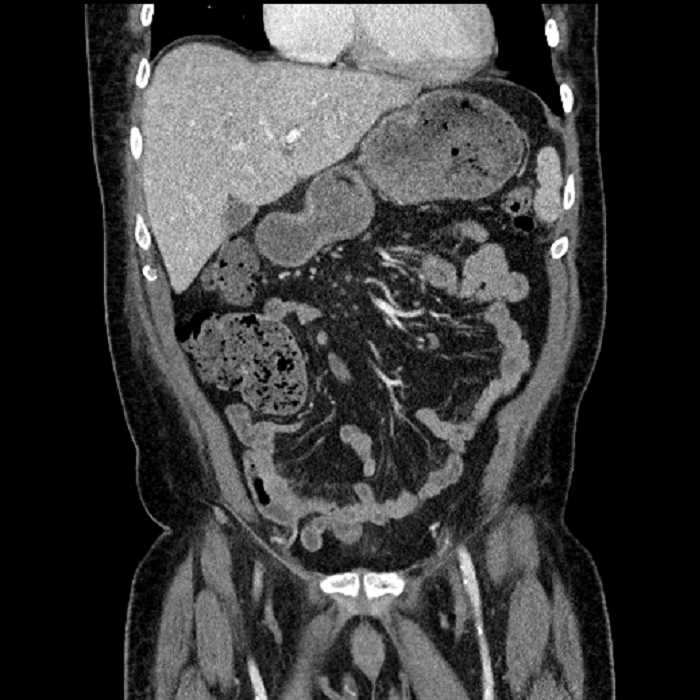

Age: 63

Sex: Male

Indication: Abdominal pain

• Large fluid density structure in hepatic segments 7 and 8 measuring 10 x 7 x 7 cm with internal septation and circumferential ill-defined low density compatible with edema

• Peripherally enhancing subcapsular collections along the anterior margin of the left hepatic lobe measuring 3 x 1 cm and 2 x 1 cm

• Mild mural thickening of a segment of the sigmoid colon with adjacent fat stranding and a 1.5 cm fluid and gas collection along the tip of an inflamed diverticulum

• Loss of the normal fat plane between this collection and adjacent loops of small bowel, which demonstrate mural thickening

• Hepatic abscess

Acute sigmoid diverticulitis complicated by a small contained perforation and a large abscess in the right hepatic lobe. Additional small subcapsular abscesses along the anterior margin of the left hepatic lobe.

Additionally, loss of the normal fat plane between the peridiverticular collection and adjacent thickened loops of small bowel raises the potential for an enterocolonic fistula.

Hepatic abscess showing the double target sign with low density internally surrounded by a thin inner enhancing rim (red arrow) and ill-defined outer low density rim (yellow arrow). Blue arrow indicates an internal septation. Red arrows: additional smaller subcapsular abscesses. Red arrow: focal contained perforation associated with diverticulitis.